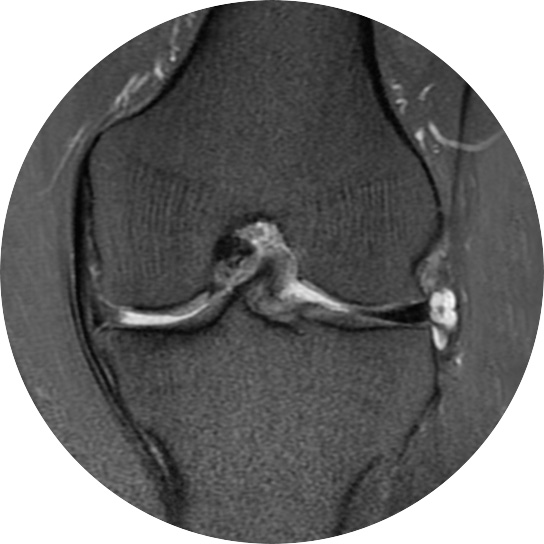

연골손상의 단계를 결정할 때 사용하는 ICRS 단계에서 3단계 미만의 연골손상에 사용하는 방법으로 울퉁불퉁한 표면을 다듬어 주는 정도의 수술법입니다.

4단계 이상일 경우 미세천공술을 기본으로 시행하며, 미세천공술로 나온 본인의 골수줄기세포와 함께

연골 생성을 촉진할 수 있는 “재료”를 같이 주입하는 치료를 시행합니다.

손상된 연골 부위에 작은 구멍을 뚫어 골수에서 나오는 줄기세포를 이용하여 연골 재생을 유도하는 방법으로 근본적으로 섬유연골(정상연골보다는 약한 연골)로 재생된다고 알려져 있습니다.